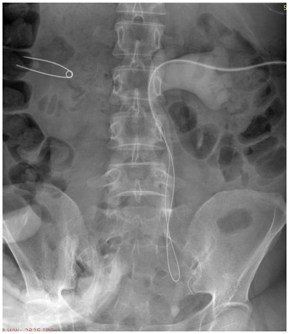

Previous studies report minor (early and delayed) complication rate ranging from 28-60% excluding pain.6 In our study minor complications rate was 50.72% and excluding pain (17.39%) decreased it to 33.33% suggesting decrease of complications with combined guidance technique. Procedure related complications continue to be widely reported regardless of the type of imaging employed for guidance.6 Rates vary from 25-60% and higher values include late (more than 24hours after PCN) minor complications such as those related to tube malfunction, leakage, dislodgement and incrustations. In our study the procedure related complications were seen in 15.94% PCN and included IVC puncture, perinephric haematoma and haematuria Figure 4. Complications such as infection (10.5%) are also described in literature25 with perinephric abscess rates to be as high as 15%, however in our study no such complication was reported. Complications such as ineffective drainage (12.5%) may require revision secondary to malposition or blockage of the catheter.26,27 Although the percutaneous approach under image guidance has a high technical success rate, long term management of nephrostomy catheters is cumbersome and is associated with an inferior quality of life as compared with internal stents.1 Catheter related complications were commonly encountered (39.13%) in our study also.

Precise point of entry was confirmed by a performing a nephrostogram and once the access into target calyx was confirmed the needle was exchanged over 0.035 Terumo guide wire. The tract was serially dilated, catheter introduced and guide removed after confirming correct placement of catheter tip. The nephrostomy tube was secured and urobag attached. Post procedure nephrostogram was performed Figure 2.

Figure 2a Radiograph showing the puncture needle in the dilated opacified PCS.

Figure 2b Radiograph showing the guidewire in the opacified PCS and the ureter with the needle in the PCS.

Figure 2c Radiograph showing dilator over the guidewire inside the opacified PCS.

Figure 2d Radiograph showing malecot’s catheter in the opacified PCS.